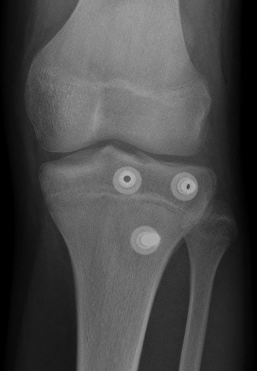

Type III

Technique

Restore articular surface

- may need to visualize joint line with arthrotomy / arthroscopy

- pass guide wires for screws into epiphysis and tibial tubercle

- image intensifer to ensure reduction / growth plate protection / no penetration to posterior neurovascular structures

- secure with AP screws in tibial epiphysis through vertical split in patella tendon

- unicortical fixation to protect popliteal artery

- restore tibial tuberosity with screws +/- washer